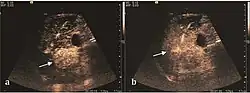

On CEUS examination, early HCC has an iso- or hypervascular appearance during the arterial phase followed by wash out during portal venous and late phase. There are studies showing that the wash out process is directly correlated with the size and features of neoplastic circulatory bed. Thus, highly differentiated HCC illustrates the phenomenon of late or even very late "wash out" while poorly differentiated HCC has an accelerated wash out at the end of arterial phase. It is therefore mandatory to analyze all these three phases of CEUS examination for a proper characterization of liver nodules. Tumor wash out at the end of the arterial phase allows the HCC diagnosis with a predictability of 89.5%. Some authors consider that early pronounced contrast enhancement of a nodule within 1–2 cm developed on a cirrhotic liver is sufficient for HCC diagnosis. These results prove that for a correct characterization of the lesions it is necessary to extend the examination time to 5 minutes or even longer.

2D ultrasound, Doppler ultrasound and especially CEUS can play an important role in pretherapeutic staging, particularly when sectional imaging investigations (CT, MRI) provide uncertain results or are contraindicated. During the interventional procedure, ultrasound allows guidance of the needle into the tumor. CEUS allows guidance in areas of viable tissue and avoids intratumoral necrotic areas. CEUS also allows assessment of therapeutic effect immediately post-procedure (with the possibility of reintervention in case of partial response) . To accurately assess the effectiveness of treatment it is mandatory to compare the tumor diameter before therapy with the ablation area. The volume of damaged tissue must be higher than the initial tumor volume. CEUS appearance is that of central nonenhanced area showing a peripheral homogeneous hyperenhanced rim due to post-procedure inflammation. 24 hours after the procedure the inflammatory peripheral rim is thinning and the necrotic area appears larger than at the previous examination. Thus, a possible residual tumor may appear more evident. Residual tumor has poorly defined edges, irregular shape, and the tumor diameter is unchanged. Residual tumor tissue is evidenced at the periphery of the tumor as an eccentric area behaving as the original tumor at CEUS examination, with arterial hyperenhancement and portal and late wash-out. Ultrasound examination 24 hours after the procedure, including CEUS, can show apart from the character of the lesion any potential post-intervention complications (e.g. active bleeding).

Local recurrence is defined as recurrence of a hyperenhanced area at tumor periphery in the arterial phase, with portal and late wash-out. Sometimes, especially for HCC treated by alcoholization (PEI) hyperenhanced septa or vessels can be shown inside the lesion.